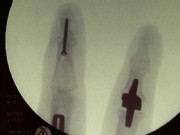

Middle and right: stiffening in the functional position with the V-tek regular screw. Eliminates pain and visually shows a satisfying result.

Below: End-joint stiffening in the index finger and middle-joint endoprosthesis in the middle finger